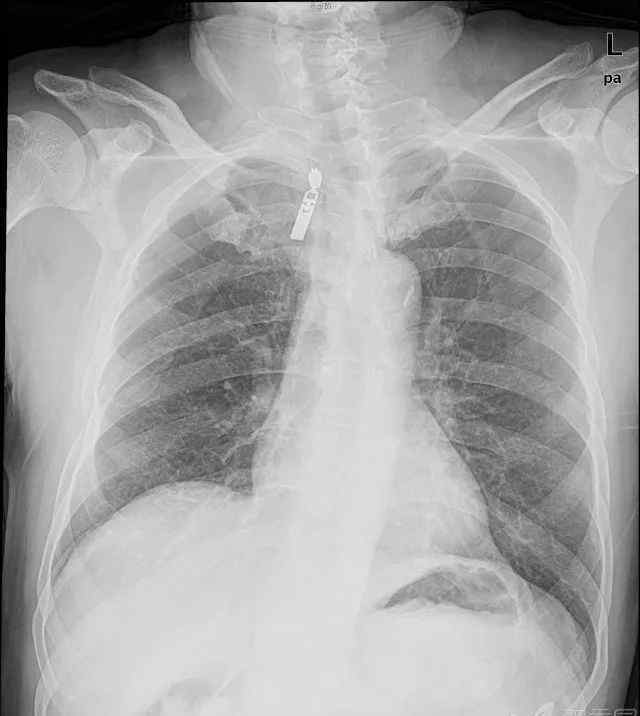

病例2:间歇性咳嗽咳痰1周,伴有发热和右胸痛加重2天

当天照的片子如上,CT左为下图,抗炎6天后CT右为下图。

你对这个案子怎么看?

看了轮廓征的解释,病例2的诊断准备出来了吗?右肺中叶大叶性肺炎。